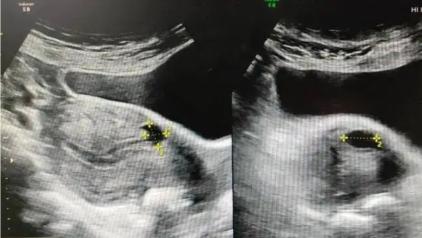

首先给该患者做了超声检查(图一),检查结果:子宫前壁处肌层回声不均匀,可见大小约0.5*0.4cm无回声,与宫腔相通,内膜线居中,厚约0.3cm,子宫前壁剖宫产处无回声,提示:剖宫产处憩室形成。根据王女士的剖宫产史,以及出现的经期延长,阴道异常出血等症状,结合超声检查结果,明确诊断为子宫憩室。

子宫前壁处肌层回声不均匀,可见大小约0.5*0.4cm无回声